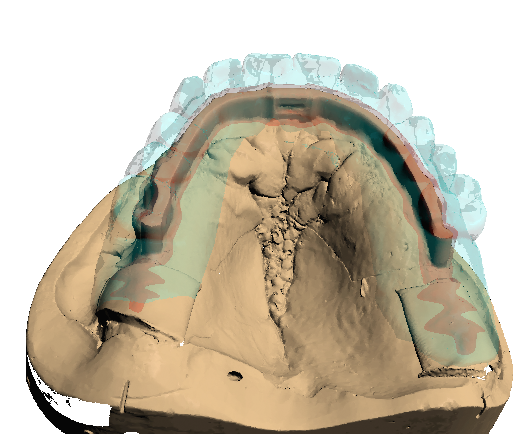

Teleskopierende Brücken im digitalen Ablauf hergestellt.